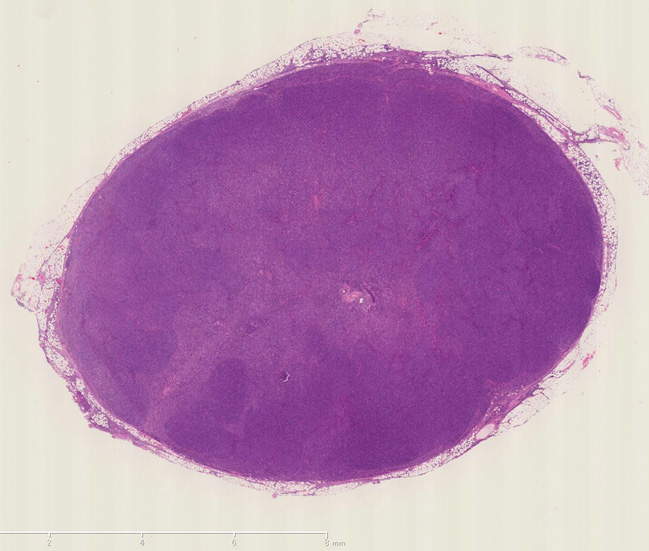

腹膜リンパ節生検組織

病理組織診断: Adult T cell lymphoma---> 腹膜リンパ節の病理組織所見

ATL_HE01web.jpg 病理組織像のPDFファイルが見られます。

小型から中型リンパ球を背景にHodgkin cell, Mirror image cellなどHodgkin lymphoma, LPに似た組織像を呈する症例のようです. CD3, CD4がびまん性に陽性を示します.